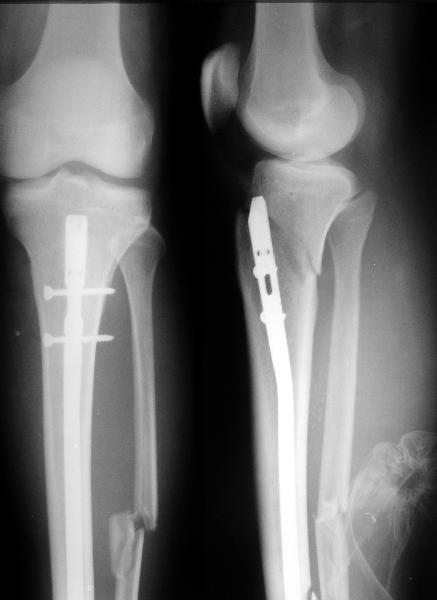

Делали остеосинтез большеберцовой кости гвоздем мужчине 30 лет, 2 недели после травмы, открытый 2Б перелом в нижней трети. Уже когда увезли из операционной, на ополнительном снимке выявился перелом метафиза. Завтра надо будет фиксировать.

I applied a simple Ilizarov frame, and after reduction inserted a locking screw into a 45 degree hole and two AP screws "miss a nail".

X-rays attached.

Так и сделали. Плюс винт в 45 градусное отверстие и два в передне-заднем направлении. Снимок в приложении выше.